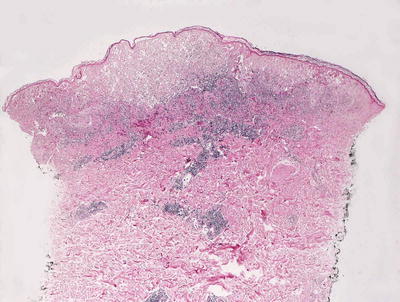

Early lesions demonstrate a moderate degree of epidermal acanthosis with significant pallor within keratinocytes at superficial levels of the epidermis (Figs. 12.7, 12.8 and 12.9). Within these cells, viral cytoplasmic inclusions are seen. Intraepidermal vesicles are often present secondary to marked edema within the dermis. The dermis demonstrates a proliferation of thin-walled vessels with a surrounding infiltrate of lymphocytes, histiocytes, and rare eosinophils and plasma cells [80, 81]. As the lesions evolve, epidermal necrosis is almost invariably present, often prominent in the central portions of the lesions. Neutrophils are present adjacent to the necrotic foci. Viral particles are readily apparent on electron microscopy [81].

Fig. 12.7

An acanthotic and spongiotic epidermis overlies a dense lymphohistiocytic inflammatory infiltrate in orf

Fig. 12.8

Prominent epidermal spongiosis and dense inflammation are seen in orf